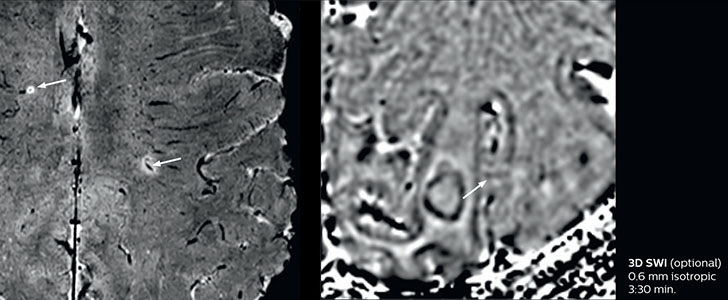

The abbreviated MS protocol for brain is only around 9 minutes, so in case of suspected multiple sclerosis, one or two more advanced sequences may be added, such as PSIR (phase sensitive inversion recovery) or susceptibility-weighted sequences to help us make more confident diagnoses in these inflammatory cases.

In this example, the optional 3D multishot susceptibility weighted sequence with 0.6 mm isotropic voxels is 2 lesions with a central vein sign (arrows) and one lesion with a phase-rim sign (arrowhead). The total scan time, including SmartBrain and axial PD/T2 3mm, is 11:10 min. and is 18:30 min. with the optional 3D PSIR and 3D SWI multishot included.